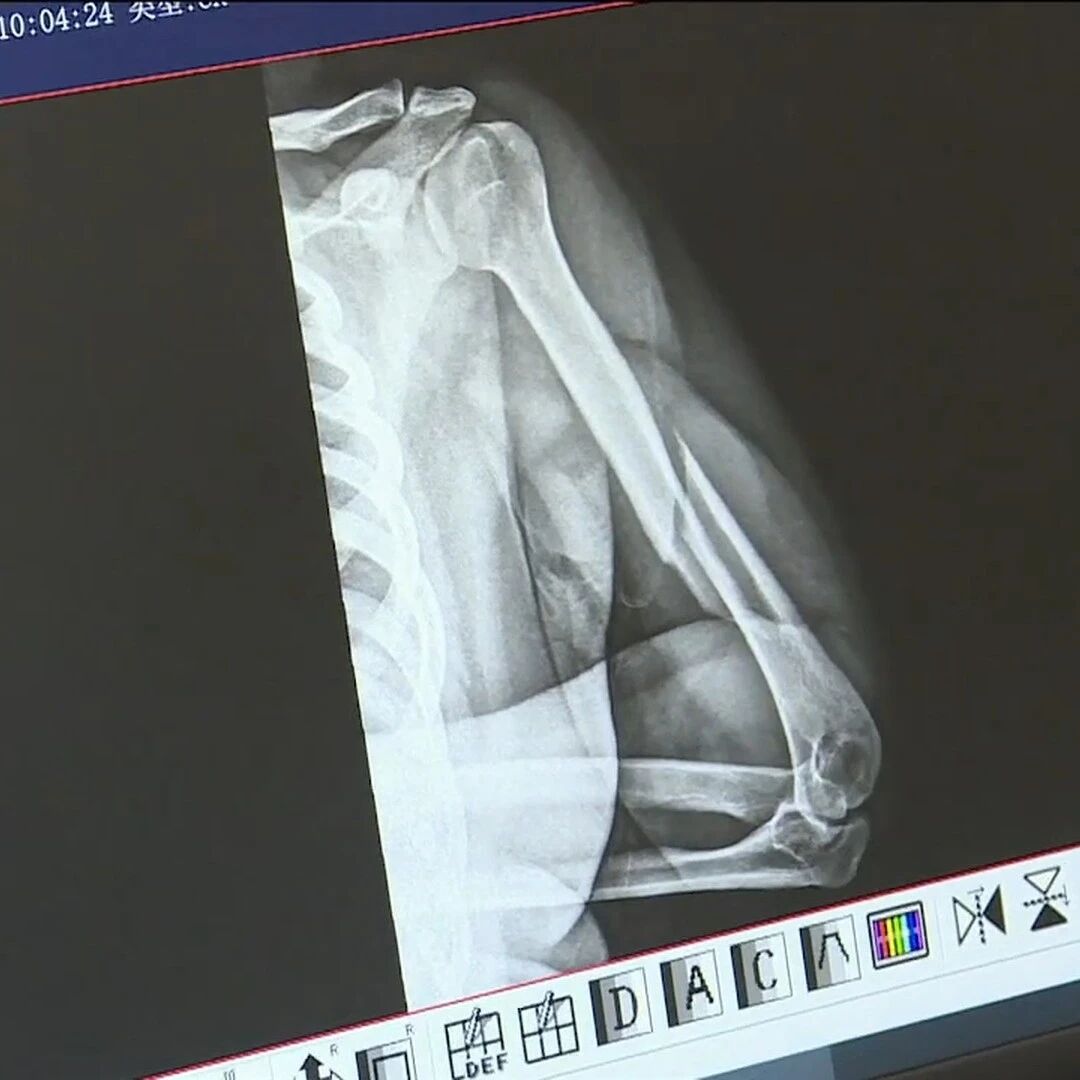

泉州一小伙掰手腕比赛时当场上臂骨折,医生:典型的因扭转暴力导致的骨折,肌肉更发达对自身冲击力更大